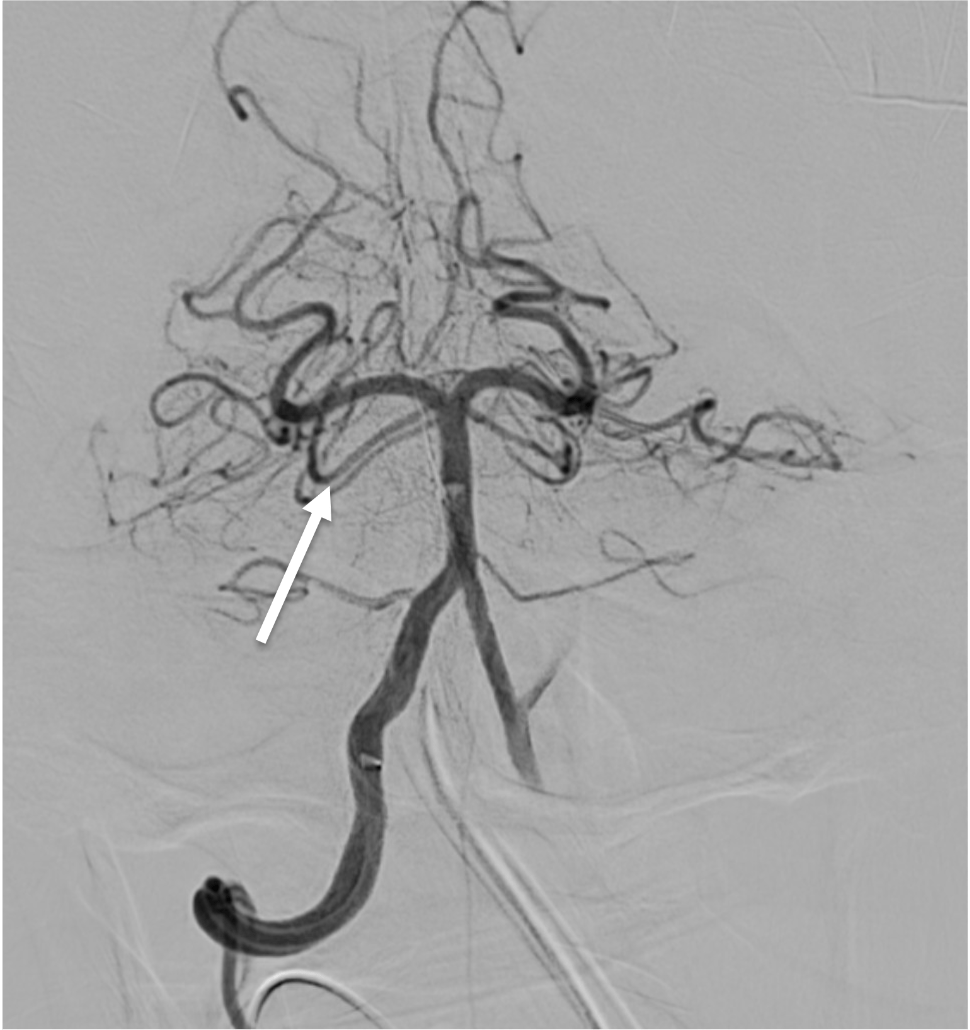

Which vessel is the arrow pointing toward?

Anterior choroidal artery